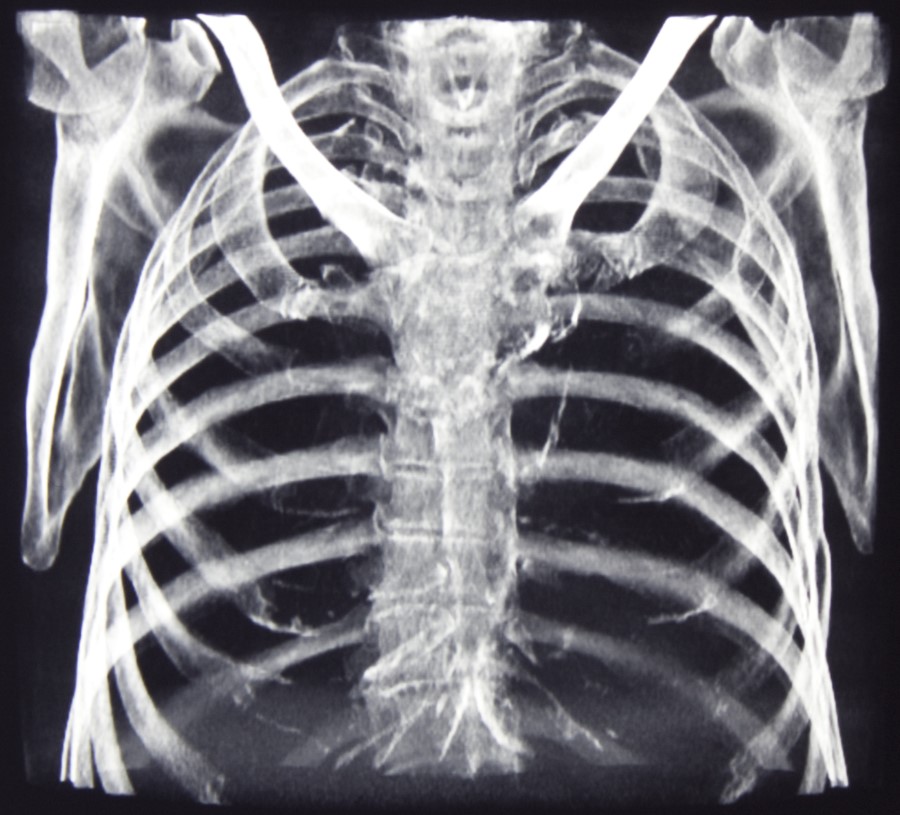

ఎదిగిన వయస్సులోని ఒక వ్యక్తి మానవ అస్థిపంజర వ్యవస్థ ఎన్ని ఎముకలతో ఉంటుందో మీకు తెలుసా? ఎదిగిన వయస్సులోని ఒక వ్యక్తి మానవ అస్థిపంజర వ్యవస్థలో 206 ఎముకలు ఉంటాయట. మానవ అస్థిపంజరం శరీరం యొక్క అంతర్గత చట్రం. ఇది పుట్టినప్పుడు సుమారు 270 ఎముకలు కలిగి ఉంది - కొన్ని మొత్తం ఎముకలు కలిసి పోయిన తరువాత ఈ మొత్తం 206 ఎముకలకు పెరిగిన వయస్సు తగ్గిస్తుంది. అస్థిపంజరంలోని ఎముక ద్రవ్యరాశి 21 ఏళ్ల వయస్సులో గరిష్ట సాంద్రతకు చేరుకుంటుంది. అప్పుడు ఈ 206 ఎముకలు వున్నట్టు. శ్రీ.కో.